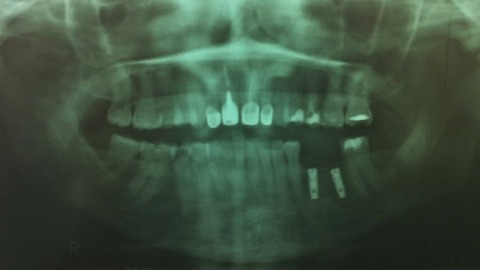

Even with perfect care of your teeth there is always going to be slow deterioration of your teeth. Friction, wear and tear, stress, and corrosion (or any combination of these actions) can cause erosion of the tooth surface and enamel.

All of these actions can cause the need for dental implants, dental veneers, or other dental procedures to help preserve your smile. Obamacare and other government insurance programs that getting these dental procedures done are not cosmetic and not required, therefore they are not covered.

I would love Barrack or Michelle to have the need for dental implants, denture implants, or a full mouth restoration and then tell the US population that going to the dentist is not mandatory and is just cosmetic. I would love for them to have to dig in their pockets for the $60,000 or more for a full mouth restoration in the USA that comes out of savings.